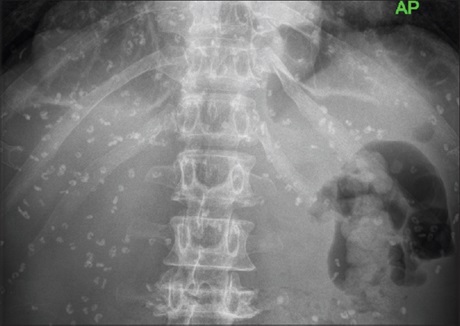

Pentastomiasis is a parasitic zoonotic disease caused by the larval stages of pentastomes, most often Armillifer armillatus. Human

infections are rarely symptomatic, and diagnosis is usually made incidentally. We report here, the case of a 60-year-old man who was

diagnosed with human pentastomiasis while being worked-up and treated for multiple myeloma. The diagnosis was made radiologically based on the characteristic multiple crescentic/C-shaped opacities seen on the abdominal and chest X-rays in keeping with Armillifer species infection. He also had the compatible history of exposure to and consumption of snake meat. This is the first documented case of human pentastomiasis at our facility and to the best of our knowledge the first to be associated with snake‑eating in Ghana.